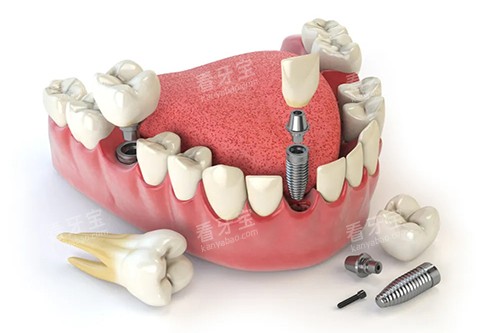

例如,在牙齿种植方面,医生会在术前对患者进行齐全的口腔检查和评估,制定科学合理的种植方案,采用可靠的种植技术和优质的种植材料,确保种植手术的成功几率和安心性。

种植方面

许多患者对大连马泷齿科的牙齿种植技术赞不绝口。

一位姓张的先生,由于意外导致牙齿缺失,在大连马泷齿科接受了种植牙手术。

他表示:“在马泷齿科种牙,我非常放心。

医生的技术很娴熟,手术过程中几乎没有什么疼痛感,而且种完的牙齿和真牙几乎没有区别,咀嚼功能也修养得很不错。

术后医生还经常回访,关心我的修养情况,服务非常周到。”

另一位李女士也分享了她的种植牙经历:“我之前一直担心种植牙会有风险,但是在马泷齿科询问后,医生给我详细讲解了种植的过程和方案,让我消除了顾虑。

手术很成功,现在我的牙齿已经完全修养了,感谢马泷齿科的医生们。”